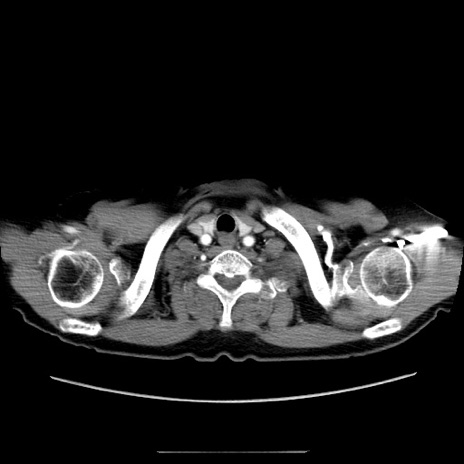

症例5(横断像)

【症例】70歳代女性

【主訴】お腹が張る

【現病歴】1週間くらい前から腹部膨満の自覚あり。昨日夜から増悪したため、本日救急外来受診。

【身体所見】意識清明、BT 36.5℃、BP 165/106mmHg、HR 80bpm、SpO2 98%、腹部:膨満、軟、自発痛・圧痛なし、触診にて不快感あり、腸蠕動音:減弱

【データ】WBC 12600、CRP 1.04